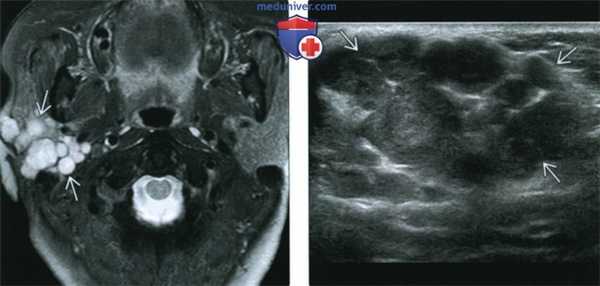

(Слева) На аксиальной МРТ (Т2ВИ FS) во внутреннем околоушном пространстве определяется опухоль овальной формы с неоднородным гиперинтенсивным сигналом. Степень интенсивности сигнала неспецифична для ДСО, такой же сигнал может наблюдаться в других паротидных опухолях.

(Справа) На аксиальной MPT (Т1ВИ) в глубокой доле околоушной железы определяется большая опухоль с промежуточным сигналом. ДСО глубокой доли могут достигать огромных размеров, оставаясь не обнаруженными. Обратите внимание, что окологлоточный жир остается различимым в виде белого полумесяца с внутренней стороны от опухоли.

4. УЗИ при доброкачественной смешанной опухоли околоушной железы:

• Хорошо отграниченная опухоль однородной низкой эхогенности:

о Визуализируется лишь при локализации в поверхностной доле

о ДСО большего размера неоднородно гипоэхогенны